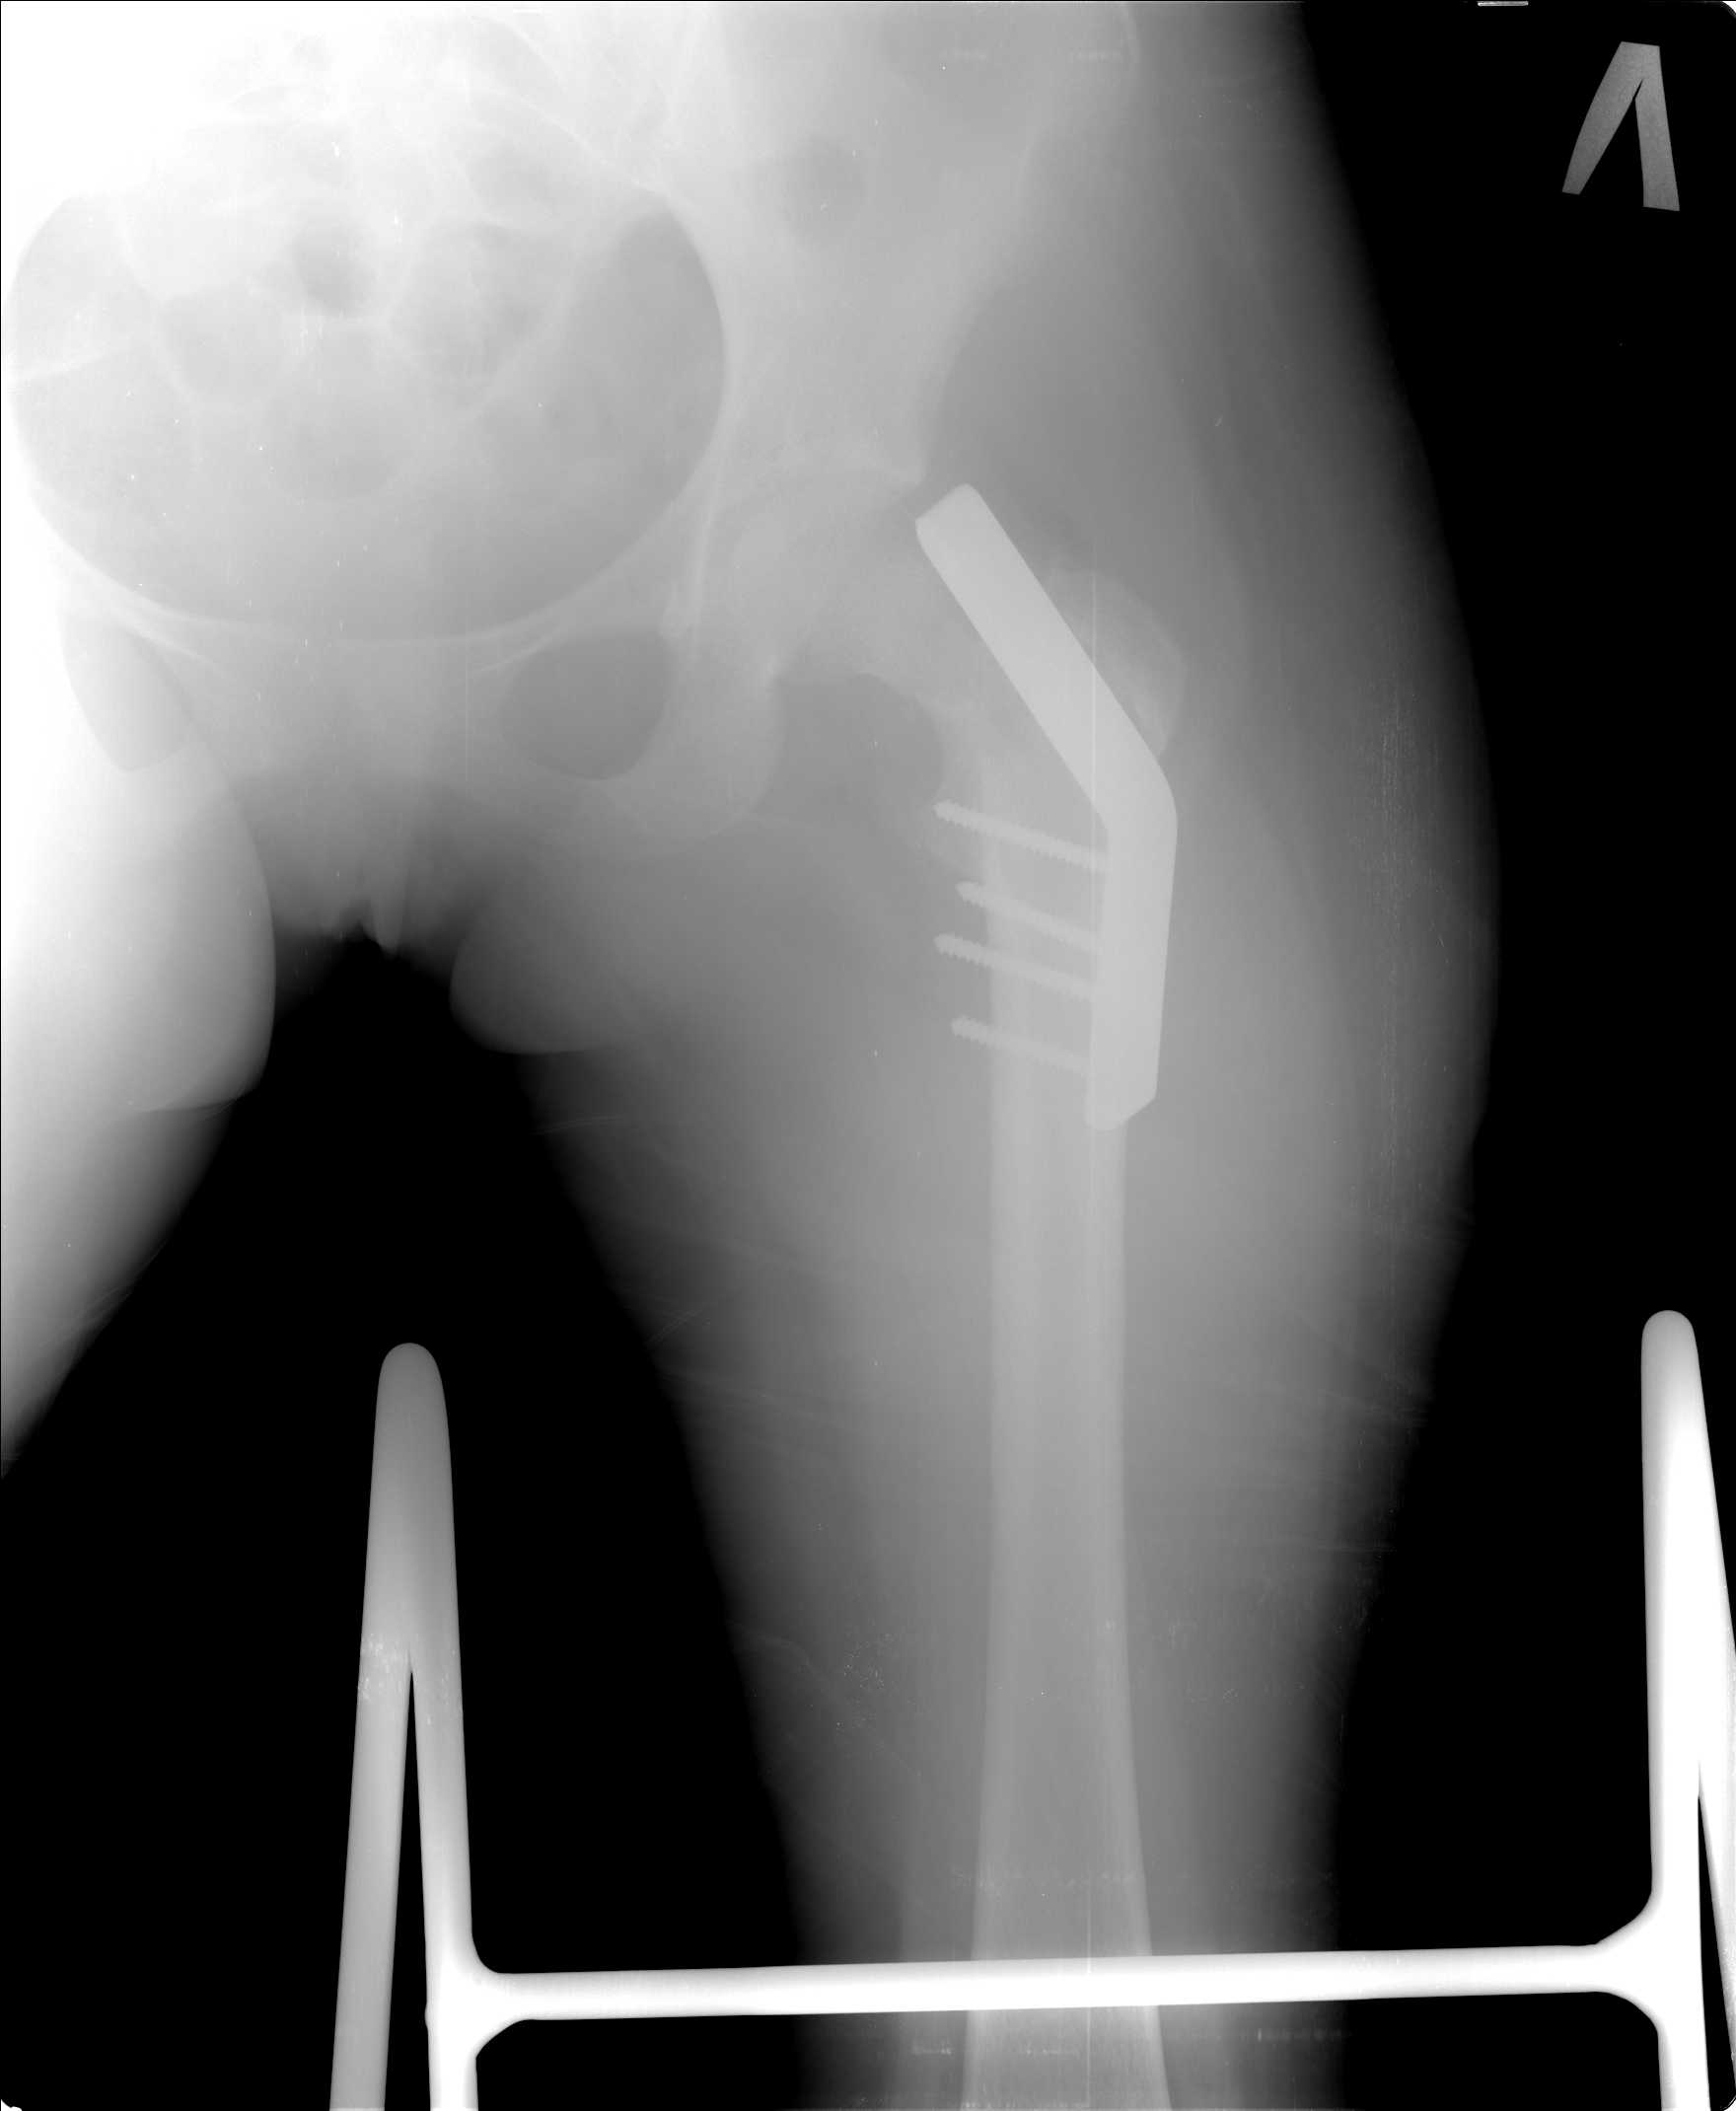

Добрый день уважаемые коллеги. Во такая ситуация. Девушка 19 лет травму получила в мае 2016г (изолированная травма, трансцервикальный перелом шейки левого бедра). Соматически здорова. Лечилась по месту жительства скелетным вытяжением в течении 1 месяца.

Затем переведена в наше учреждение. 18 июня выполнена операция, детали где , кто и как уточнять не имеет смысла( из протокола операции: выполнялась передняя артротомия, репозиция под визуальным контролем) . Учитывая характер выполненного остеосинтеза, после операции постельный режим 6 недель. Снимки в хронологии все выкладываю. КТ контроль сделан 2.09.16. для оценки состояния головки бедра. Помогите, определиться с дальнейшей тактикой.

Думается несколько вариантов:

1) удаление металлоконструкции, корректный реостеосинтез такой же конструкцией, похоже так же, с открытой репозицией, времени много прошло, закрыто не удасться поправить.

2) Учитывая срок может лучше удалить конструкцию, остеотомия в вертельной области ( по методике А.Н. Челнокова) и фиксация что имеем из PFN ( есть только Sanatmetal Fi-Can)

Межвертельную остеотомию оптимально было сразу и делать. Сейчас еще длина потерялась, сползло бедро проксимально. Так что да, надо делать вальгизирующую остеотомию. А перед ней - закрытую репозицию, т.е. вернуть ситуацию ближе к той, что была при поступлении.

Чудо!!! С собой не хотят так, если что? На хрена месяц вытяжения??? Гамму ставьте. Хотя тут фифти-фифти..